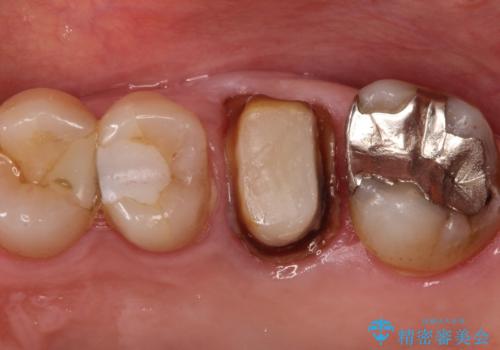

- 定期検診にて被せものと歯との隙間に虫歯を発見した患者様です。

根管治療から被せもの治療(ベレッツァ)まで行いました。(根管治療は林院長に依頼)

妥協せずにすべての治療を行うことで最終的な被せものの適合を高める事ができます。